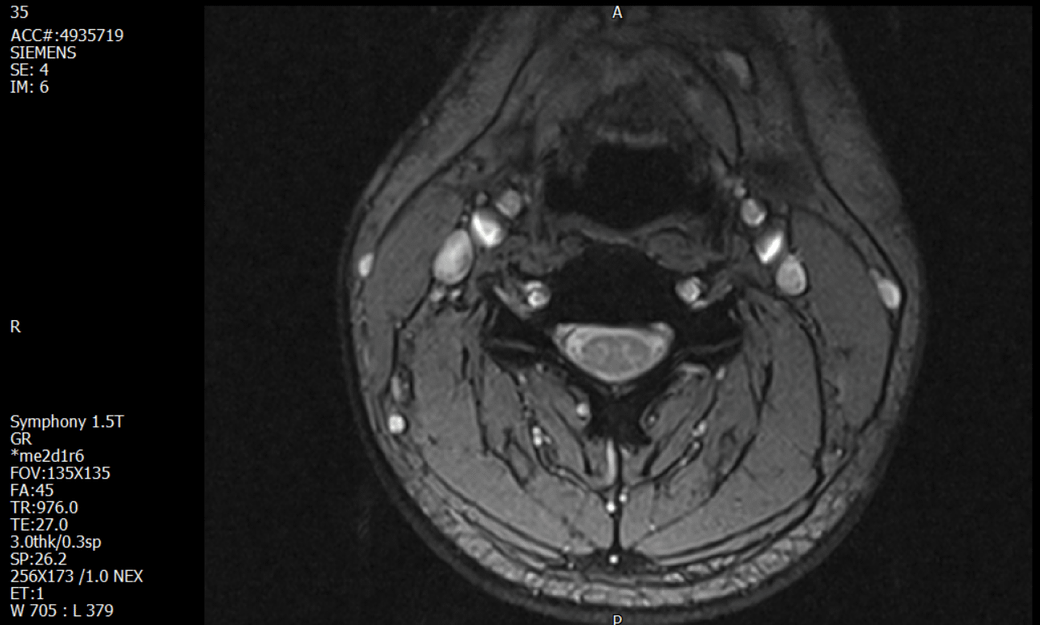

경추 요추 디스크 MRI판독 부탁드립니다.

- 3개월전 좌측 상지 저림(힘빠짐) 발생. 이틀뒤 에 좌측 하지 저림(힘빠짐) 발생.

-11월, 증상발생 직후 잠실소재 척추전문병원 MRI 요추경추 촬영 후 신경외과 박사 진료, 허리는 매우 건강, 경추는 퇴행성 진행되고 있지만 디스크라고 보기 어려움. 신경막만 살짝 건드리는 정도고 이 정도로 힘빠짐이나 저림이 오지 않고 원인은 다른 곳에 있을 가능성.

1. MRI 상 , 경추와 요추에 디스크가 있나요? 있다면 좌측 팔과 다리에 저림 및 힘빠짐을 줄 정도인가요?

• 2번 째 사진

• 1. MRI 사진을 보았을 때 디스크를 의심해볼 수 있는 소견이 살짝살짝 보이긴 합니다만, 상하지의 저림 및 힘빠짐을 유발할 정도인지는 솔직히 회의적입니다.

2. 영상의 퀄리티는 나쁘지 않아 보입니다. 굳이 재촬영을 하실 필요는 없어 보입니다.

3. 개인적으로는 디스크로 인한 증상이 아닐 것으로 보나, 만약 디스크가 맞다면 우연하게 목과 허리 디스크 발병이 이틀 간격을 두고 나타났을 가능성을 생각해야 하는데, 현실적으로 그 가능성이 높지 않습니다.

4. 말씀하신 것처럼 특히 요추부 MRI는 디스크를 찾기 어렵습니다.

상기 MRI 소견으로는 심한 증상을 보일 정도는 아니며 디스크의 가능성은 적어보입니다.